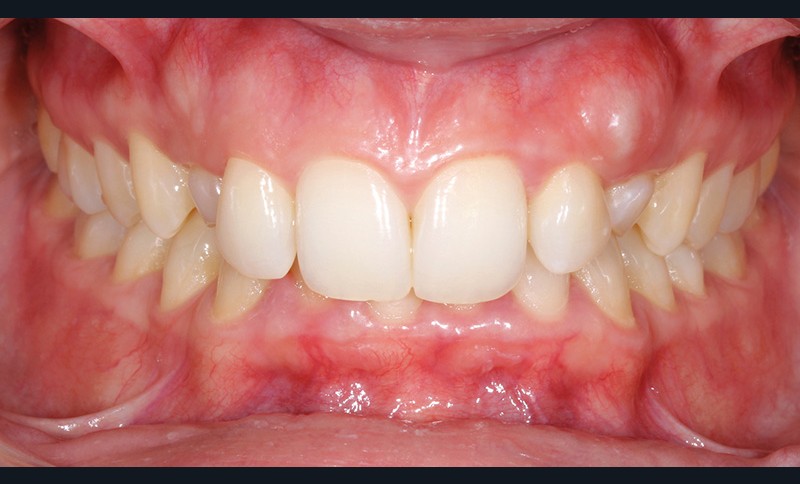

Aline se présente à la consultation pour une demande esthétique concernant ses deux canines lactéales qu’elle trouve trop petites et trop blanches (fig. 1a). Elle présente une classe II squelettique légère sur un schéma méso-divergent. D’un point de vue dentaire, une supraclusion est associée à une classe II d’Angle complète à gauche et de 4 mm à droite. Les canines maxillaires sont incluses (une vestibulaire et une palatine), avec persistance de leurs dents lactéales sur l’arcade (fig. 1b-h).

Traitement multi-attaches et contention

Un protocole orthodontico-chirurgical avec avancée mandibulaire est envisagé pour assurer un bon soutien labial, mais cette option est refusée par la patiente qui craint un visage trop carré. Concernant l’inclusion des canines maxillaires définitives, plusieurs thérapeutiques sont envisageables : 53, 63, 13, 23, ou 53, 63, 14, 24 peuvent être extraites, avec pour conséquence une classe II thérapeutique au niveau des molaires en fin de traitement. Cependant, la patiente souhaite mettre en place ses canines incluses pour conserver tout son capital dentaire et rétablir un idéal fonctionnel et esthétique au niveau des dents antérieures (fig. 2).